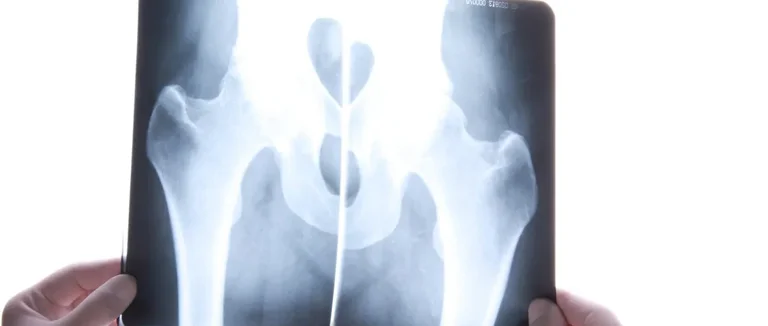

Absorptiométrie à Rayons X à Double Énergie (DXA)

La DXA est la méthode de référence pour mesurer la densité osseuse. Ce test, simple et sans douleur, utilise des rayons X. Il évalue la densité des os, surtout à la hanche et dans la colonne vertébrale.

Les résultats sont donnés sous forme de T-scores. Ces scores comparent la densité osseuse d'une personne à celle d'une personne jeune et en bonne santé.